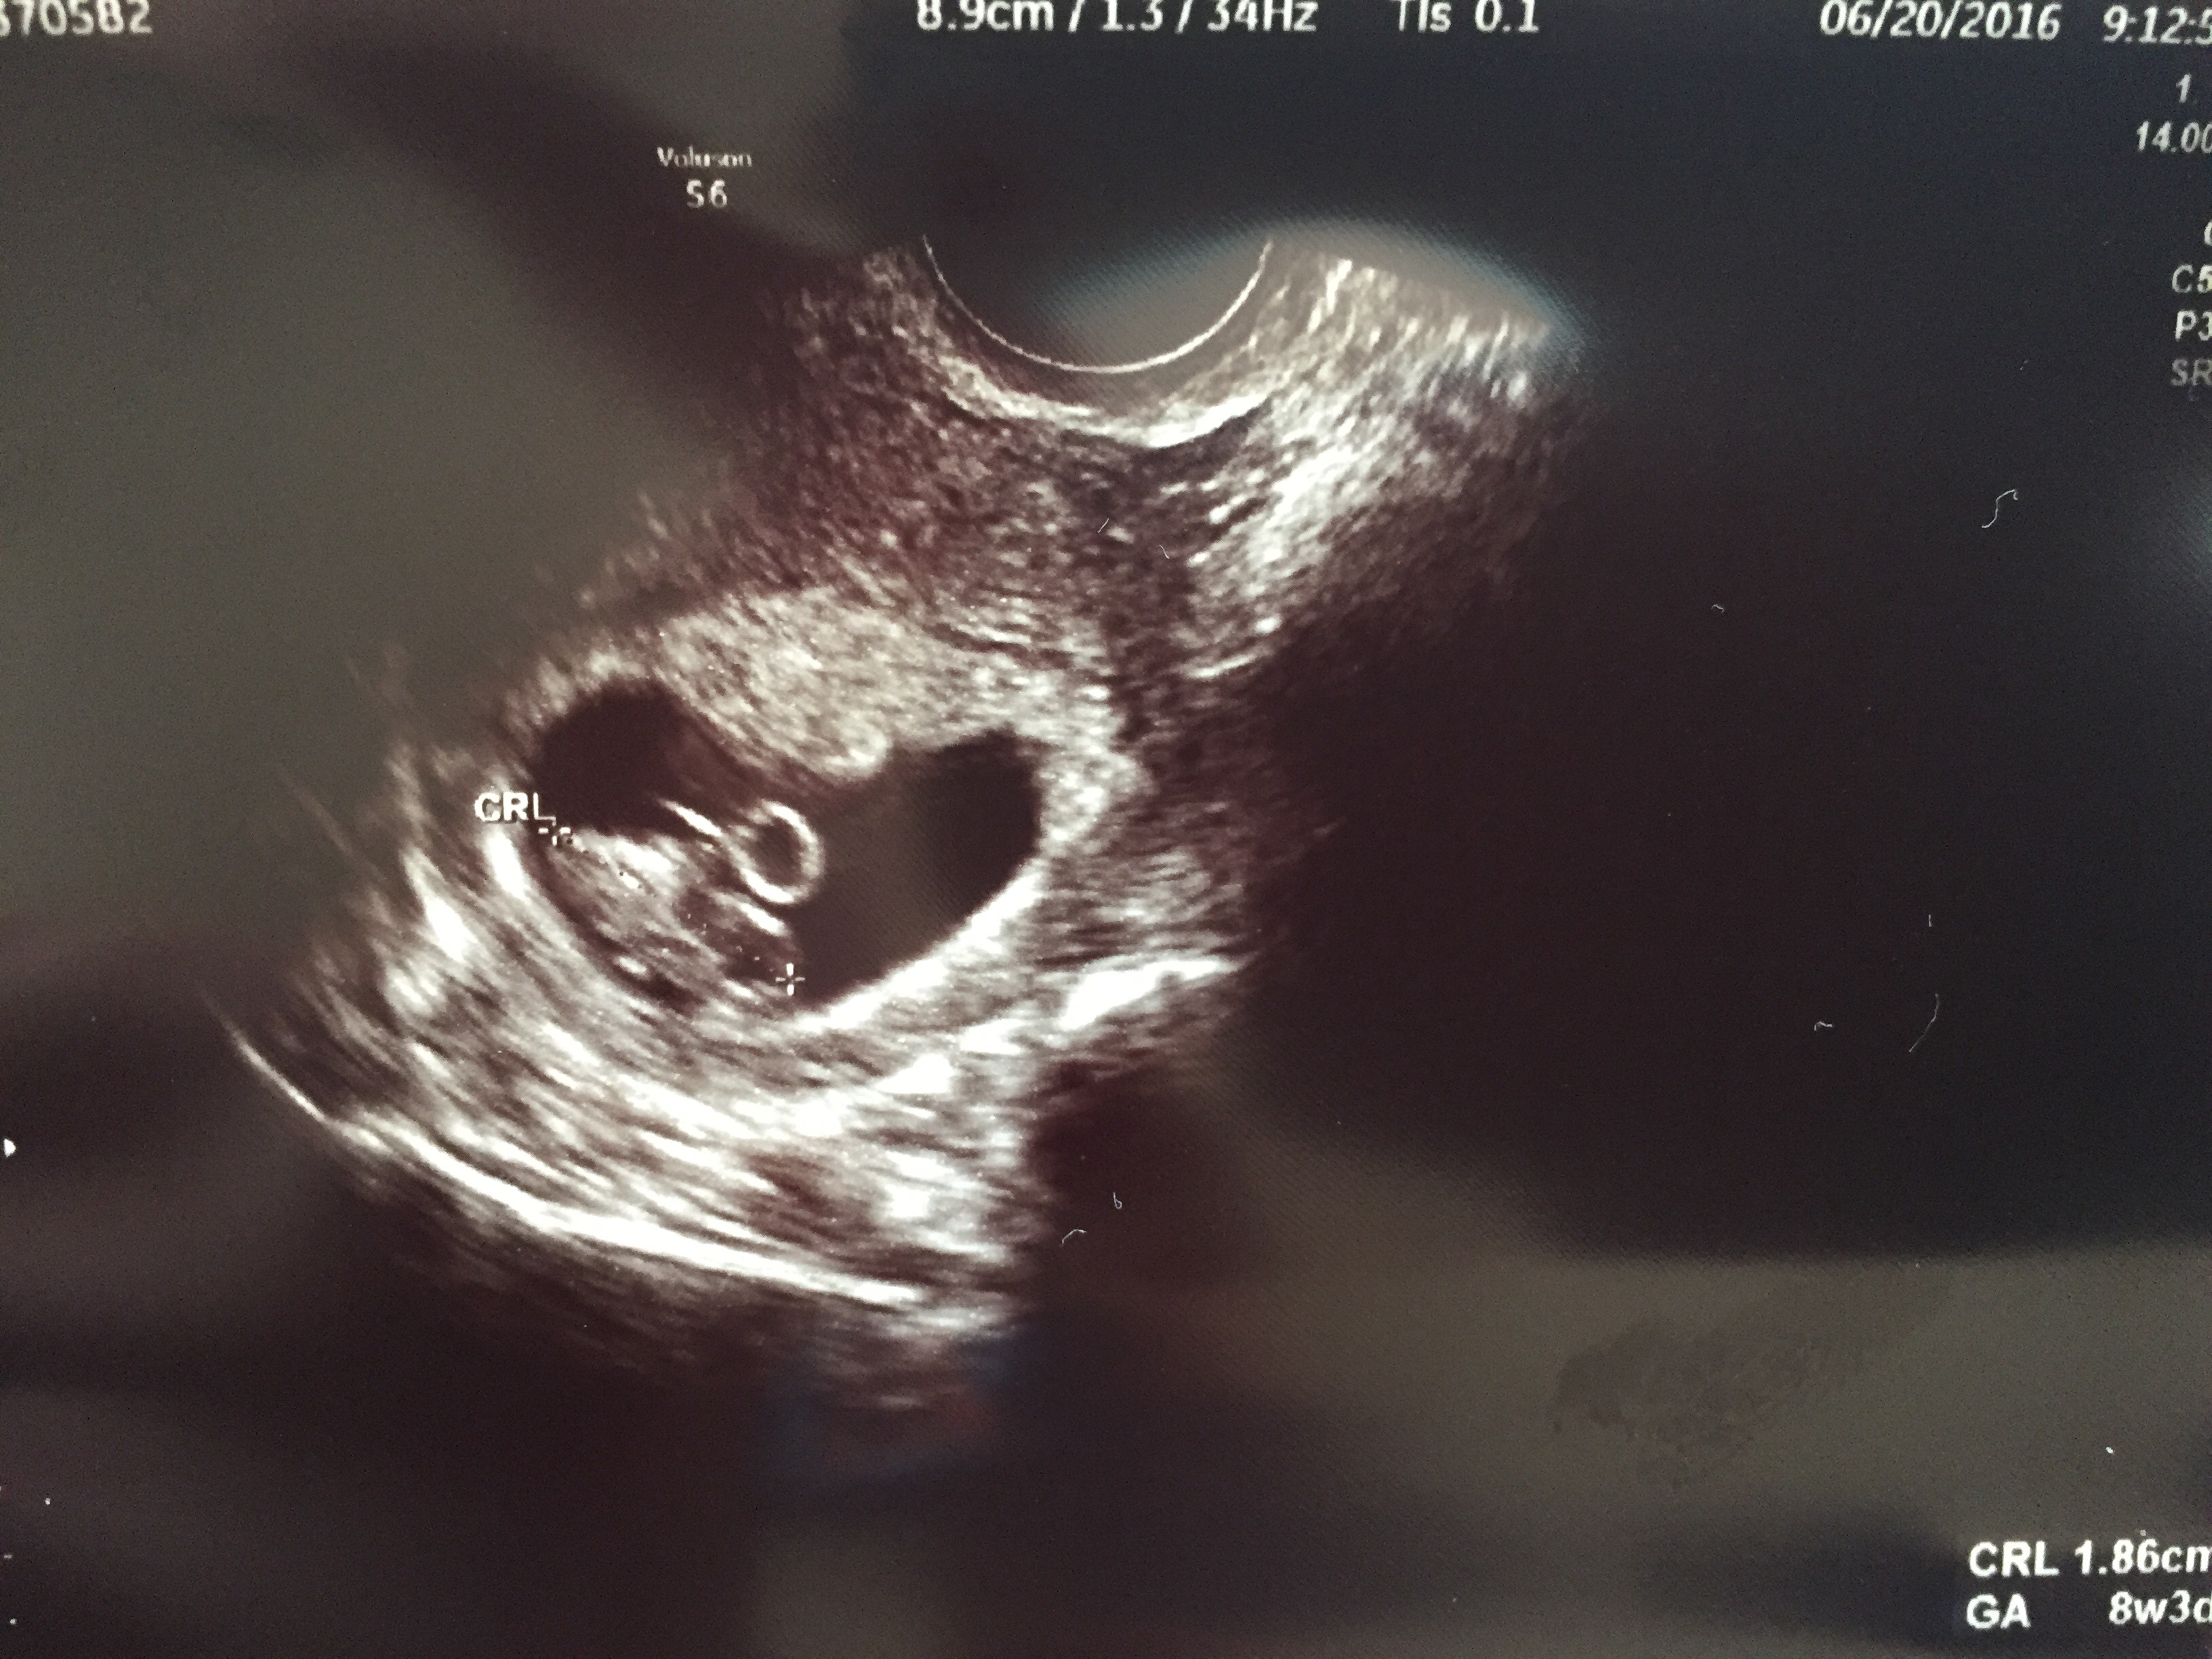

We saw our little embie earlier this week and boy did it grow since we saw it for the first time just 2 weeks ago!! It actually looks like something other than a dot — now it’s more in a blob state, lol.

But according to the apps I’m reading, our baby is growing arms, legs, getting rid of its tail, and even has eye lids!! Holy cow!

We did have a minor scare when we had our ultrasound. For a few seconds we couldn’t hear a heartbeat. Both our hearts dropped. Turns out the speakers were turned low and the heartbeat is very strong (171) but still – just makes you realize how vulnerable we still are. I asked my friend Terri “do you ever just not feel scared” and she said “nope, always a worry.” Just makes you think even more what a true and amazing miracle life really is.